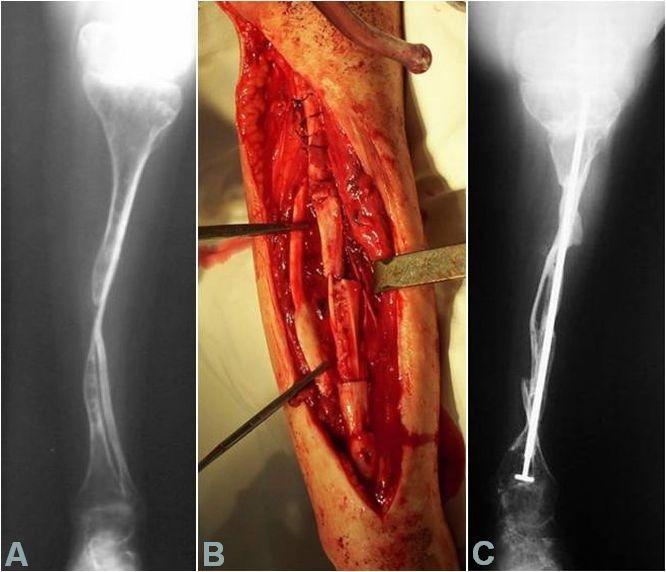

In the above-mentioned period, from the OI patients who are in the evidence of our clinic, 32 were operated on, totaling 81 surgeries. Out of these, 28 patients, aged 2-27 years, have benefited from reconstructive surgery of the pelvic limbs. Sofield-Millar osteotomies were practiced and 69 Sheffield telescopic rods were implanted in 25 patients and 43 surgeries. The coxa vara / valga correction using the Sheffield rod was applied in 6 patients and 8 hips, respectively. Circular or monoplane external fixators were used in 7 patients for the correction of deformities, lengthening and arthrodiastasis. 9 patients have benefited from various forms of bone transplant: pedicled grafts, auto- and/or allografts. An original bone reconstruction procedure is currently being studied and will be useful in the treatment of large bone defects and the thickening of the gracile diaphyses, which consists in practice of a massive contribution of free bone grafts, auto- and/or allogenic, bone substitutes and, in selected cases, periosteal substitutes, in a composite stratified construction. Postoperatively, 15 patients are able to walk while being supported by crutches or walking frames, 5 patients walk independently and 8 are still wheelchair-bound. It is important to mention that 8 children who were preoperatively dependant on the wheelchair are now walking!

在上述期间,在我们诊所登记的OI患者中,有32人接受了手术,共计81次手术。其中,28名年龄在2至27岁的患者接受了骨盆四肢的重建手术。实施了索菲尔德 - 米勒截骨术,并在25名患者的43次手术中植入了69根谢菲尔德伸缩杆。分别对6名患者的8个髋关节应用谢菲尔德杆进行了髋内翻/髋外翻矫正。7名患者使用环形或单平面外固定器进行畸形矫正、肢体延长和关节扩张。9名患者接受了各种形式的骨移植:带蒂移植、自体和/或异体移植。目前正在研究一种原始的骨重建程序,该程序将有助于治疗大的骨缺损和纤细骨干的增厚,其实际操作是大量使用游离骨移植、自体和/或异体骨替代物,以及在特定情况下使用骨膜替代物,进行复合分层构建。术后,15名患者能够借助拐杖或助行架行走,5名患者能够独立行走,8名患者仍需依赖轮椅。需要提及的是,8名术前依赖轮椅的儿童现在能够行走了!